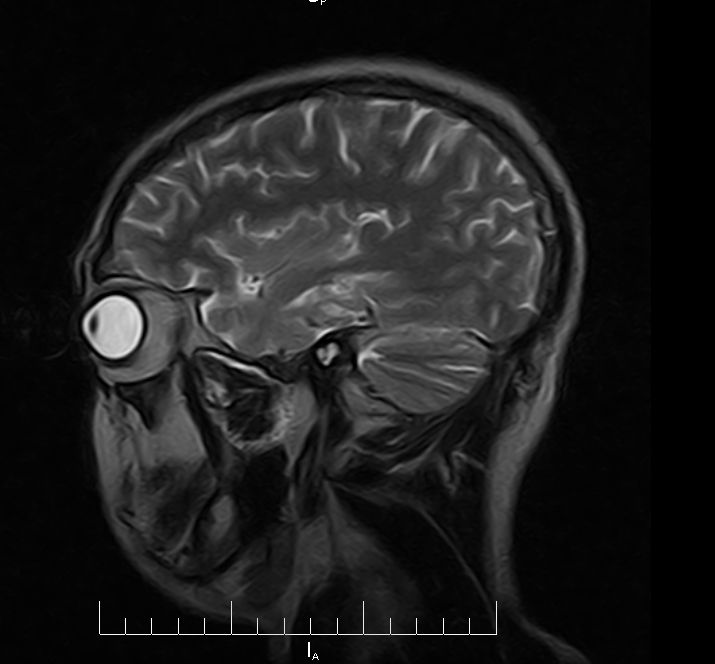

标题: MRI2379:30岁,男,癫痫10年,请各位看一下;CT示:左颞叶钙 [打印本页]

标题: MRI2379:30岁,男,癫痫10年,请各位看一下;CT示:左颞叶钙

左颞叶区见不规则点状混杂信号影

考虑血管畸形

考虑左侧颞叶脑血管畸形(avm)。----t1低等高混杂信号,t2等高信号周边较多流空血管影[冠状位明显],mra左侧大脑中动脉受压,远侧聚集.

海绵状血管瘤

支持海绵状血管瘤!